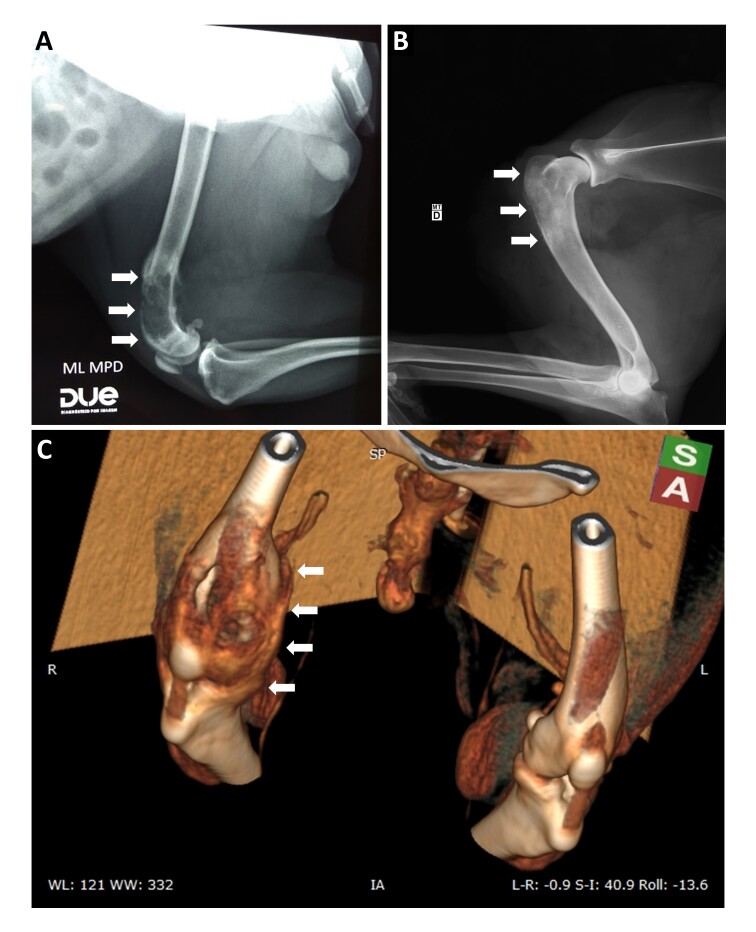

本文报告了两例母犬乳腺癌骨转移的组织病理学和免疫组织化学特征。第一个病例中的动物是一只10岁的雌性贵宾犬。体格检查发现左侧腹部尾侧(M4)和腹股沟(M5)乳腺肿块,六个月前发展。右侧骨盆肢体的影像学检查显示股骨远端部分有骨溶解。胸部x线片未见转移灶。显微镜检查结果与恶性腺肌瘤的诊断一致。股骨远端肿块的特征与乳腺肿块相似。第二个病例的动物是一只9岁的雌性杂交动物,由于疾病预后不良而被安乐死。M3, M4和M5原发肿瘤的组织病理学评估与II级筛状癌的诊断一致。肺、肝、肾、肾上腺、右肱骨干骺端近端延伸至干骺端远端、腋窝及髂内侧淋巴结实质均可见转移灶。免疫组化检测Ki67、Cox-2、ER、PR、Pan-CK、p63和HER-2在原发肿瘤和骨转移中的表达。两例细胞均有较高的增殖率,激素受体、Pan-CK和p63阳性。HER-2在原发肿瘤和骨转移中均为阴性,COX-2在原发肿瘤中均为阴性,在病例01转移中为阴性,在病例02转移中为阳性。

In the present case report, the histopathological and immunohistochemical characteristics of the two cases of bone metastasis of mammary carcinoma in bitches are described. The animal in the first case is a 10 years old female poodle. The physical examination revealed a mass in the left abdominal caudal (M4) and inguinal (M5) mammary glands with a six-month evolution. The imaging exams of the right pelvic limb revealed areas of bone lysis in the distal portion of the femur. No evidence of metastases was observed in the thorax on thoracic radiographs. Microscopic evaluations were consistent with the diagnosis of malignant adenomyoepithelioma. The mass in the distal region of the femur has characteristics similar to those observed in the mammary gland mass. The animal in the second case was a nine-year-old female mixed-breed euthanized due to the unfavorable prognosis of the disease. Histopathological evaluation of the primary tumor in M3, M4, and M5 was consistent with the diagnosis of grade II cribriform carcinoma. Metastatic foci were observed in the lung, liver, kidney, adrenal, proximal metaphyseal region of the right humerus extending to the distal diaphyseal region, and axillary and medial iliac lymph nodes' parenchyma. Immunohistochemistry was performed for markers Ki67, Cox-2, ER, PR, Pan-CK, p63 and HER-2 in the primary tumor and bone metastasis in both cases. High proliferation rate, positivity for hormone receptors, Pan-CK and p63 were observed in both cases. HER-2 was negative in the primary tumor and bone metastasis and COX-2 was negative in the primary tumor of both cases, negative in the metastasis of case 01 and positive in the metastasis of case 02.